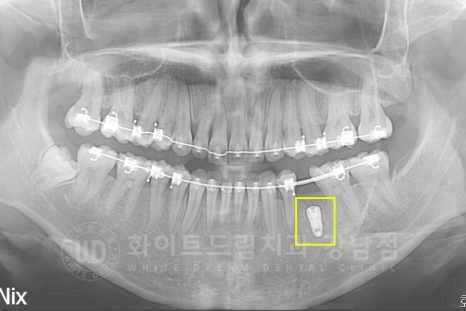

② 치아교정 계획에 맞추어 치아의 이동을 유도합니다.

교정 전 :15.08.01 / 교정 중 공간 체크 일자 : 17.02.28

교정 전 구내 사진과 비교해 보면,

악궁과 치열의 변화는 물론 쓰러졌던 치아들이 올바른 자리를 찾아간 것이 확인됩니다.

쓰러진 치아들로 공간이 없었던 35번 치아의 빈자리가 확보되었습니다. ^^

이제 임플란트 식립 일자 및 과정에 대해서

환자분 + 교정과 전문의 + 임플란트 전담 의료진 (본원 정수윤 대표원장님)

일자 및 치료 과정을 다시 한번 상의하게 됩니다.

③ 임플란트 식립 & 교정 마무리

골 소실이 많이 진행되었던 상태여서 선 뼈이식 후 → 지연 식립으로 치료가 진행될 확률도 있었는데요.

다행히 뼈이식과 임플란트 식립을 동시 진행해도 될 만큼 잇몸뼈가 회복된 상태였습니다.

※ 임플란트 수술은 본원 정수윤 대표원장님이 직접 진행하셨습니다.

수술일자 : 17.03.28